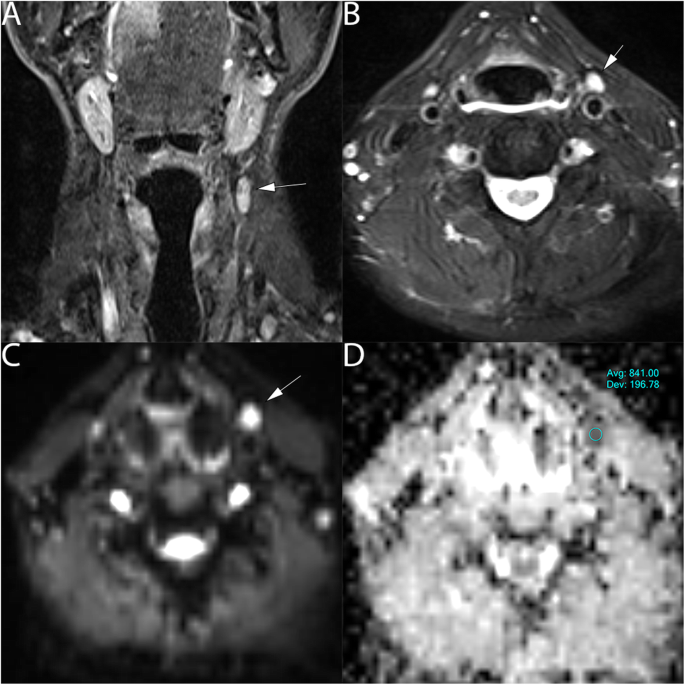

Overall, 90 lymph nodes were studied, 65 metastatic lymph nodes: minimum short-axis diameter size (6-44 mm) and maximum short-axis diameter size (7-85 mm), Figs. 2 and 3, were assessed and compared to 25 normal lymph nodes, minimum short-axis diameter size range (4-9 mm), and maximum short-axis diameter size range (6–13 mm), Fig. 4.

65 years old male with para-pharyngeal sub-centimeters lymph node positive malignancy from laryngeal SCC on the left side of the neck. a T2 coronal show the lymph node, (arrow). (B) T2 axial show the axial extension of the lymph node (6x8mm), (arrow) (c) DWI show hyperintense area at b value 800mm2/s (arrow) and (d) ADC map on the targeted lymph node show hypointense signal, an ADC value of (0.841 ± 0.19*10− 3 mm2/s)